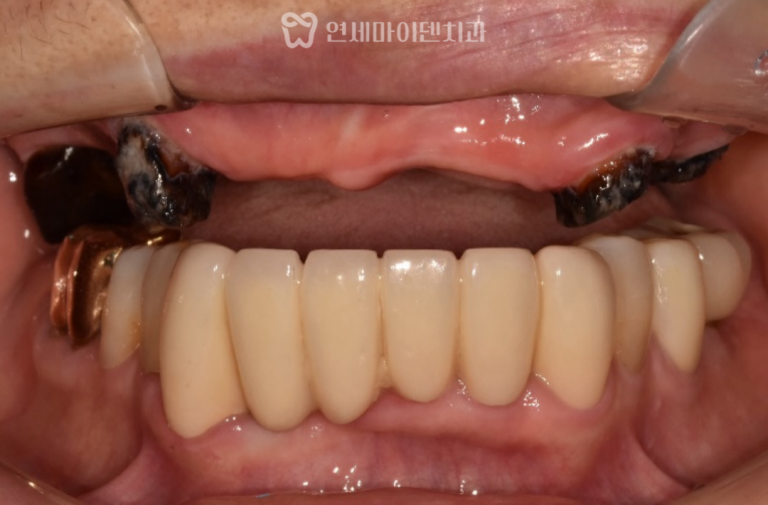

임플란트 식립

공간 확보 후에는 6번 어금니 부위에 임플란트를 식립하였고,

약 2~3개월간의 안정화 기간을 거쳐

뼈와 임플란트가 단단히 결합되었습니다.

이후에는 교정용 철사를 평평한 형태로 교체해

공간 유지와 환자의 편안함을 함께 확보했습니다.

최종적으로는

- 임플란트 크라운이 완성되었고,

- 교합과 주변 치아의 움직임 없이 안정적인 결과를 얻을 수 있었습니다.

또한 왼쪽 아래 어금니의 재신경치료 부위 염증도 호전되어,

전체적인 구강 상태가 크게 개선되었습니다.